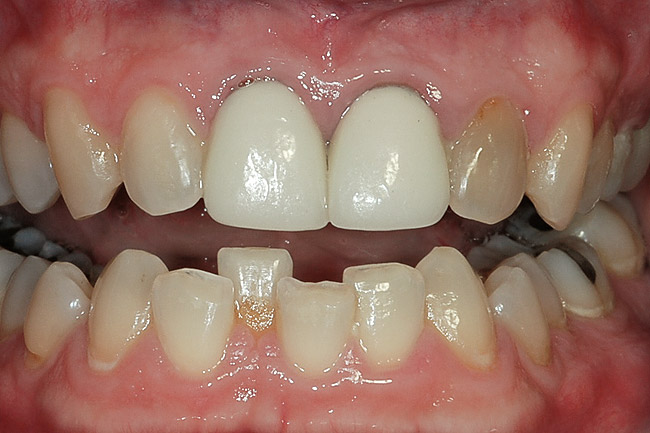

Figure 9  A reasonable match was obtained from about 8 weeks of single-tooth bleaching. Often patients discontinue treatment when the single tooth is no longer a mismatch, even if the outcome is not ideal.

Figure 9